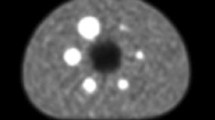

One of the novel findings in this study was physiological FDG uptake corresponding to the STN (Fig. 4). Although FDG accumulation in the substantia nigra is already known [16], this is the first study to demonstrate more avid physiological FDG uptake in the STN than that in the substantia nigra. The improved visualization is due not only to the high spatial resolution achieved by the WB SiPM-PET system and by applying a sufficiently high number of iterations for OSEM with TOF and PSF reconstructions, but also to the evaluation of FDG-PET images with reference to the 3D-FLAIR images, which are considered useful for identifying the STN [24, 25]. In the clinical setting, it is important for neurosurgeons to accurately identify the anatomical location of the STN on MRI because it is the most common target structure for deep brain stimulation, which is one of the treatment options for advanced Parkinson’s disease. Although the relationship between the degree of FDG uptake in the STN and the severity of Parkinson’s disease or the efficacy of STN stimulation remains unclear, it would be worth investigating in a future study using the high spatial resolution SiPM-PET scanner with an appropriate reconstruction method as described above.

18F-FDG accumulation in subthalamic nuclei. Coronal average 18F-FDG PET image with reconstruction of OSEM iteration 64 + TOF + PSF (left, arrows) demonstrates avid FDG uptake corresponding to subthalamic nuclei (18F-FDG PET/3D-FLAIR fusion image, middle, arrows), which are well-recognized on coronal 3D-FLAIR images (right, arrows)